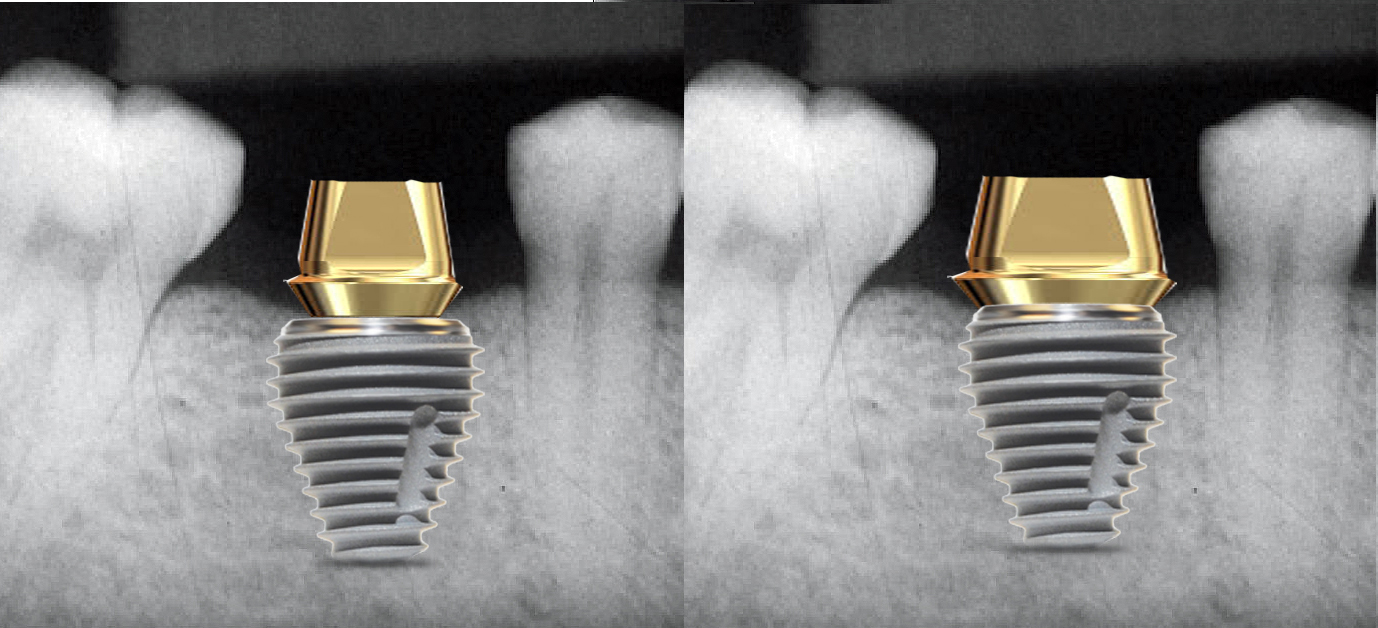

Tissue-level and non-platform-switched implants typically are not placed below the bone level (subcrestal) (Figure 3).22 Placement of such implants below the bone level is not recommended, as the bone will remodel leading to crestal bone loss in a saucerization pattern.11 This occurs in tissue-level implants because the smooth collar of the implant is not roughened for osseointegration. In non-platform-switched implants, subsequent placement of the abutment below bone level leads to remodeling circumferentially to accommodate biological width development (Figure 4).23

Fig 3. Platform switching is when the diameter of the abutment at the platform is narrower than the diameter of the implant (left). In a non-platform-switch situation, the diameter of the abutment and implant at the platform are equal (right).

Figure 3

Fig 4. Comparison of implant placement depths, which are dependent on the implant design: a tissue-level implant is shown replacing the maxillary first molar, and a deeper placement depth using an implant system with a platform-switching feature is shown replacing the second molar.

Figure 4